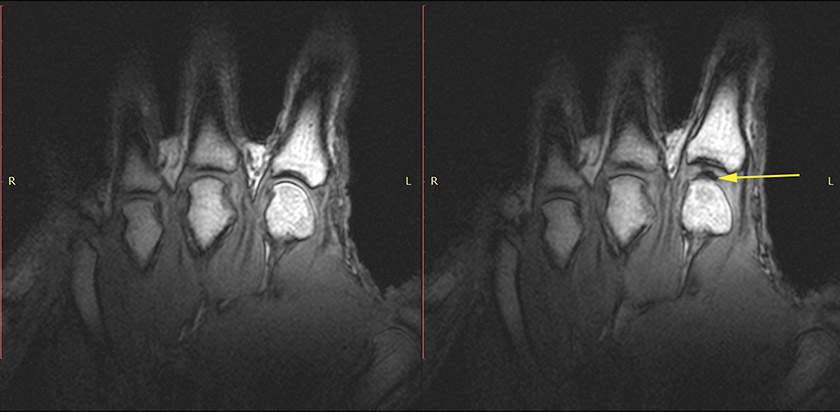

У 2015 році загадка, здавалося, була розгадана: використовуючи магнітно-резонансну томографію, канадські вчені з Університету Альберти заглянули всередину хрусткого суглоба і переконалися в тому, що звук виникає не тоді, коли бульбашки газу лопаються, а в момент їх появи. Вони пов’язали це з різким перепадом тиску в суглобі, що виникає внаслідок дуже швидкого формування газового міхура.

Передпускове проміжне з’єднання, з’єднання над отвором радіочастотної котушки (середина). Рука учасника в магнітному томографі (праворуч).

Одна і та сама рука після розтріскування з додаванням дифракційної сили після розтріскування (справа). Зверніть увагу на темну, міжчастинкову пустоту (жовта стрілка).